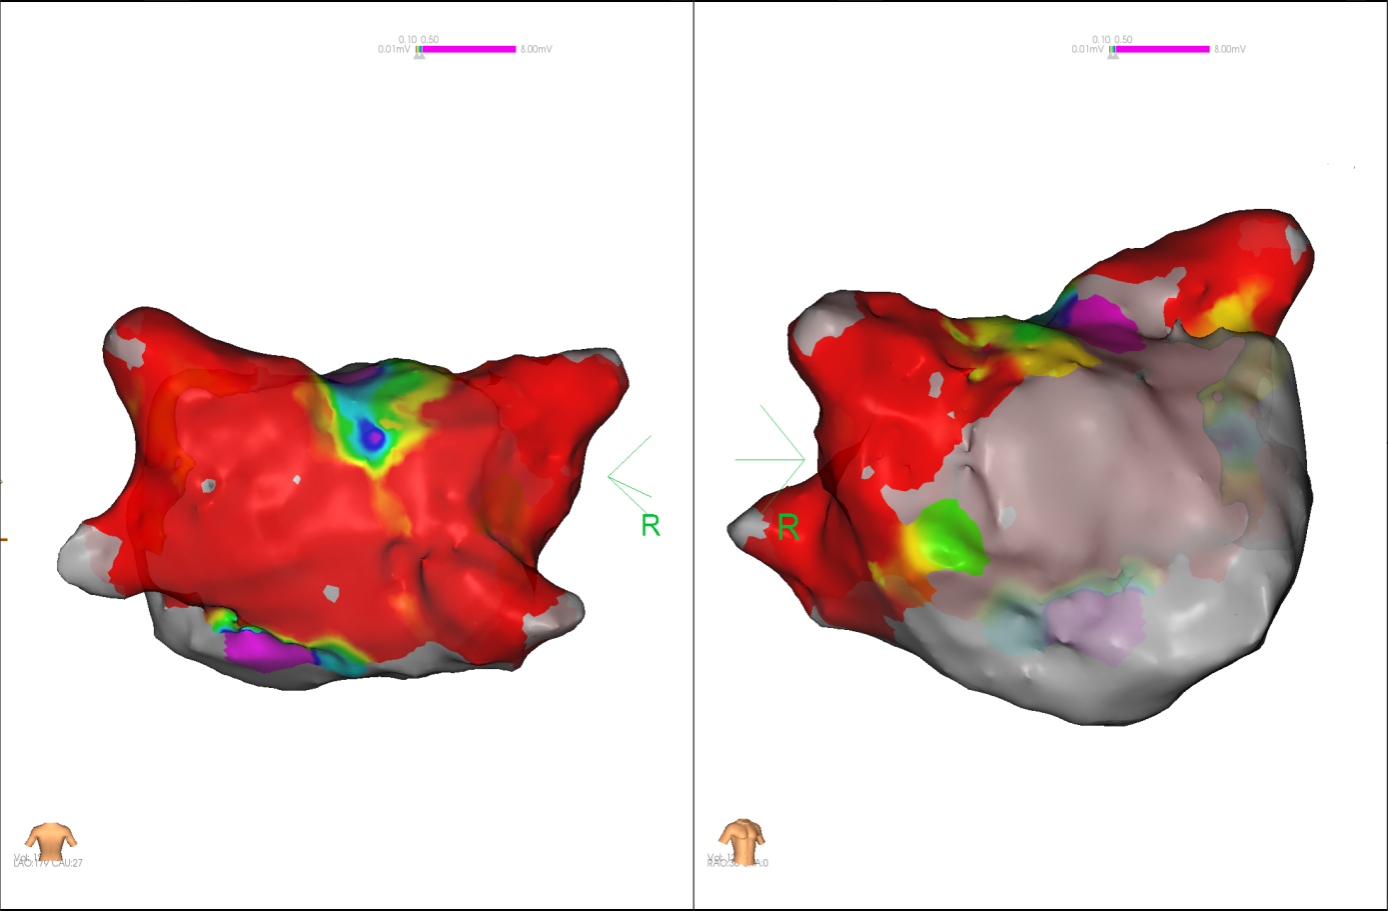

图3 PFA于右肺静脉后壁交叉消融时转为窦率,继续消融

图4 消融前后基质标测提示肺静脉消融效果明显

经充分术前评估及准备后,该患者手术在抗心衰药物持续静脉泵入、高流量吸氧支持下及麻醉、护理团队的通力配合下进行,由薛建颖、崔明亮主治医师具体实施。术中通过右侧股静脉送入心腔内超声至右心房,排除左房血栓后成功指导房间隔穿刺,沿可调弯鞘管送入锦江心脏脉冲电场消融导管至左房,构建左房三维解剖模型并行基质标测,标测显示左房基质差,分别行左侧、右侧肺静脉及后壁BOX消融。消融参数:1800v,400ms,400μs,共放电消融140次(消融右肺静脉时转复为窦性心律),验证双肺静脉均隔离。术后重新标测显示所有肺静脉均已急性阻滞,消融效果理想,肺静脉前庭损伤范围也达到了预期的标准,同时心腔内超声监测未见明显心包积液。手术仅用时30分钟,时间明显缩短,手术过程精准高效。术后患者恢复情况良好,维持窦性心律。